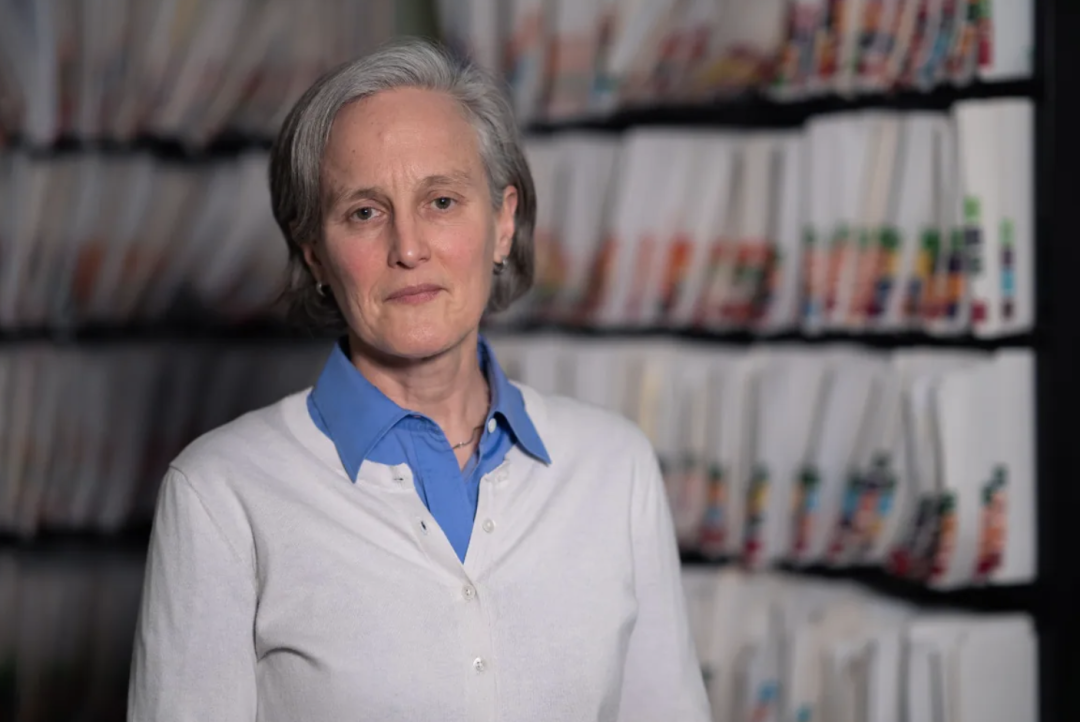

安大略省结肠癌筛查计划的首席科学家 Jill Tinmouth 博士强调,目前还没有足够的证据表明对 50 岁以下人群进行筛查的好处会超过进行肠镜检查后的潜在危害。

这是一种侵入性测试,通常在患者处于麻醉状态时将一个灵活的内窥镜插入直肠。 虽然该测试通常是安全的,并且能够发现结肠内可能发生癌变的问题,但 Tinmouth 表示,当医生切除息肉时,它会带来轻微的风险——比如出血或刺穿结肠壁。